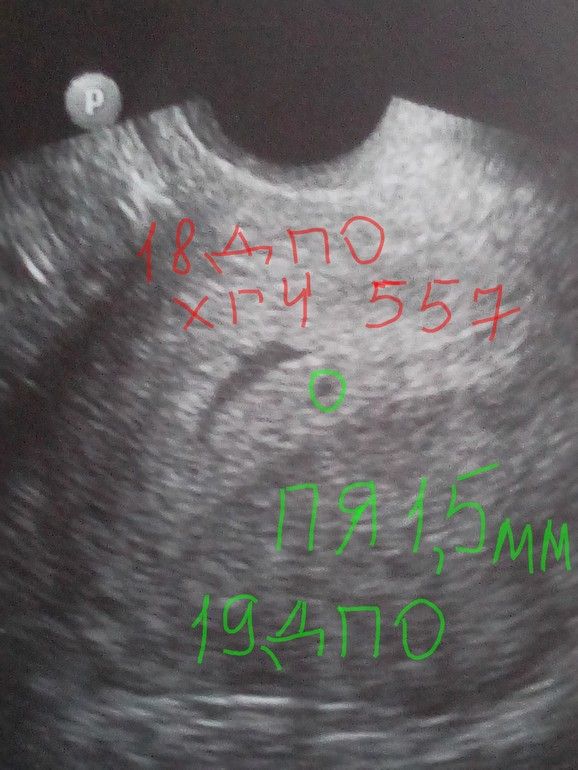

Можно идти на УЗИ смотреть плодное яйичко. Удачи🤞 Изображение